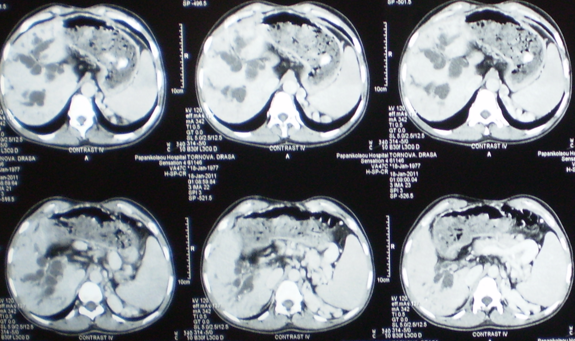

Multiple hepatic abscesses in other patients with cholecystocolic fistulas (Courtesy Dr. V. Penopoulos)